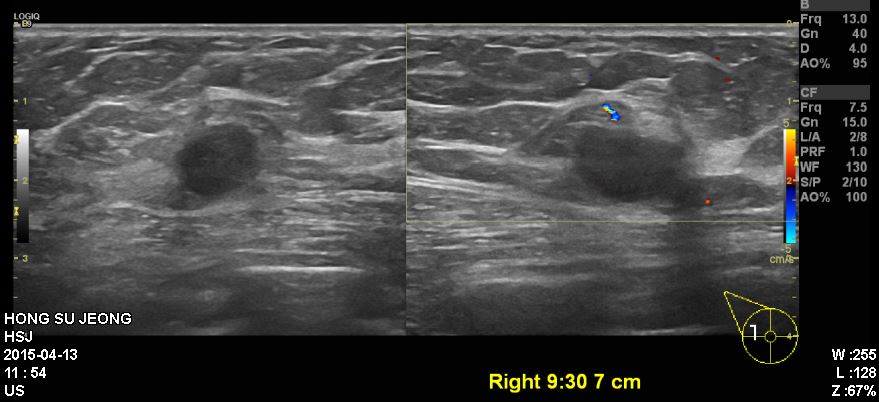

건강검진상 이상소견으로 내원하신 50대 환자 분 이십니다.

본원에서 유방 초음파 시행후 우측 9:30분 방향에 있는 혹 조직검사 시행 하였고,

결과상 유방관내 제자리 암종으로 진단 되었습니다.